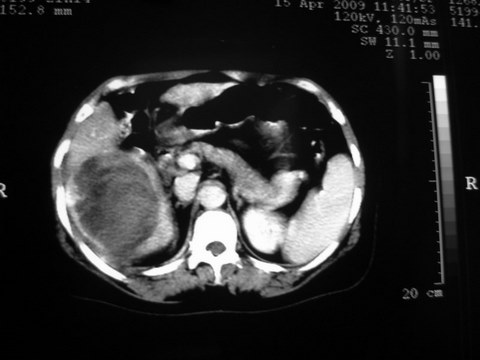

患者 女 51岁 两天前感觉上腹疼,无明显诱因,b超示肝右叶囊实性占位,边缘清楚,其内回声不均匀,ct增强如图,大家看看是什么 ,病人一年前及两月前b超检查只是提示胆囊炎

外院术后,证实肝癌合并出血

特点:1,病灶发展迅速,(2月前正常)[br] 2,囊实性,且并边界清晰光滑,呈右后叶赘生性。囊性区无强化,实性部分较多轻度强化,边界欠清。考虑囊腺癌或囊腺瘤。

出病理 中分化肝细胞癌合并出血